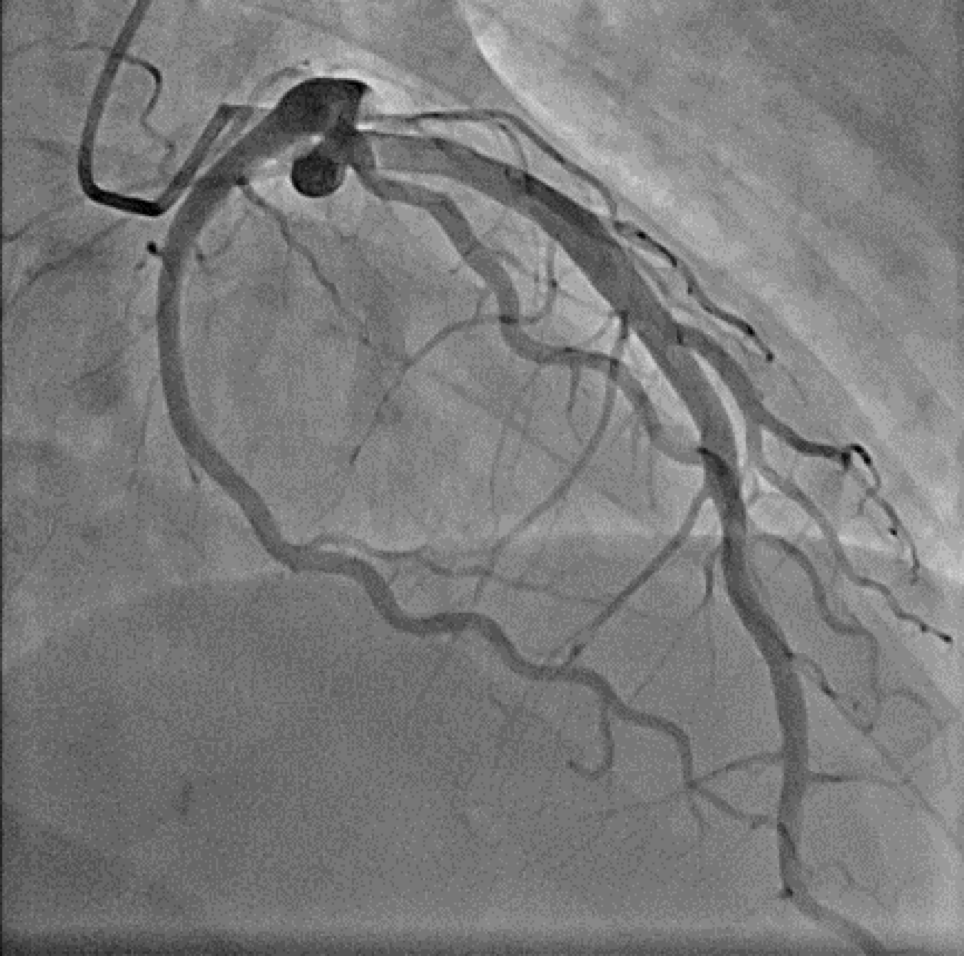

천장에 매달린 거대한 모니터에 내 심장이 실시간으로 나타났다. 마치 지하철 노선도처럼 복잡한 혈관들이 화면을 가득 채웠다.

“우관상동맥이 여기서 완전히 막혀있습니다. 99% 폐색이네요.”

화면에서 혈관이 갑자기 끊어진 것처럼 보였다. 마치 고속도로가 산사태로 완전히 차단된 것처럼.

두 번째 스텐트가 삽입되자 혈관이 마치 새것처럼 매끈해졌다. 화면에서 보는 혈류도 훨씬 부드럽게 흘렀다.

혈류가 정상적으로 회복되었습니다.

완전히 뚫린 내 관상동맥

image.png 내 심장의 인증샷, 이쁘다.